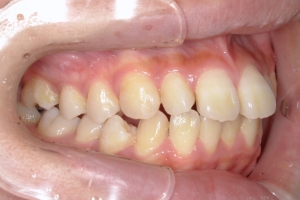

BEFORE

治療前

下の前歯が上あごの歯ぐきに当たるほど噛み合わせが深く、そのことが原因で上顎歯列の正中にすき間(正中離開)が生じていました。部分矯正ですき間を無理やり閉じても、噛み合わせが深いままでは治療後の再発リスクが高くなります。そのため全体矯正で奥歯の噛み合わせを整え、噛み合わせを浅くしつつ前歯を並べました。正中離開は戻りやすい傾向があるので、再発を防ぐため固定式リテーナーを推奨しています。